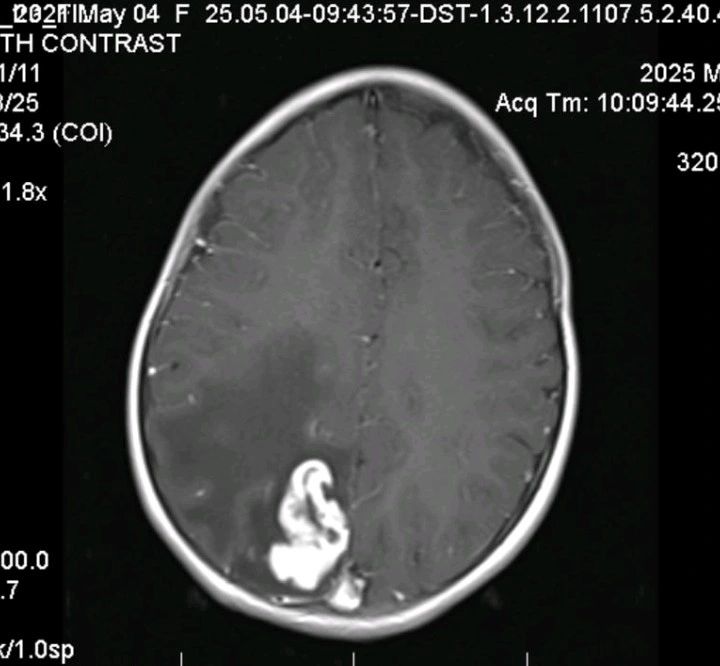

- 影像学检查: 脑部 MRI 显示明显的颅内占位伴水肿(见附图),高度怀疑为脑肿瘤。

🔪 【诊断陷阱与外科困境】 由于影像学表现极像肿瘤,且缺乏全身性或感染性体征,患儿接受了神经外科切除手术。 然而,术后病理结果却出人意料:中枢神经系统结核瘤(CNS tuberculoma)!